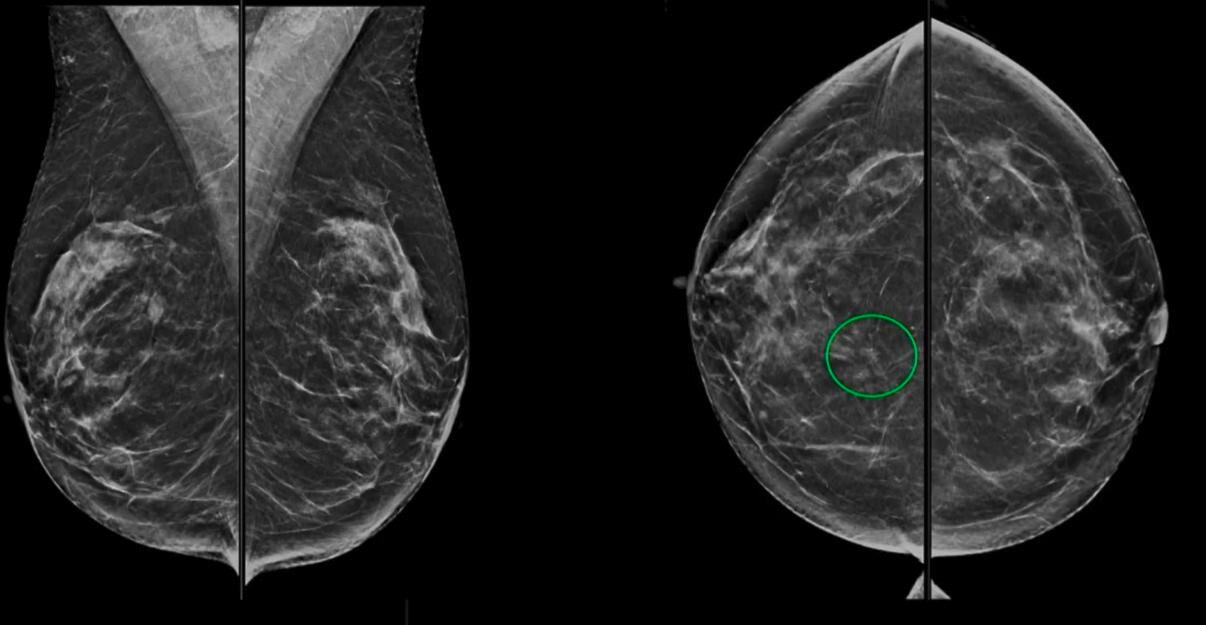

Pour les images mammographiques, le lexique et les illustrations ont été remplacés et élargis. « Les exemples d’images qui incluaient précédemment des clichés de mammographie sur film ont été remplacés par des images de mammographie numérique, de tomosynthèse et de mammographie synthétique », précise l'intervenante.

La section sur la tomosynthèse mammaire été ajoutée au chap